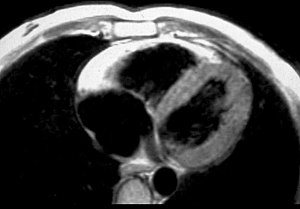

MRI[edit | edit source]

Fatty infiltration of the RV free wall can be visible on cardiac MRI. Fat has increased intensity in T1-weighted images. However, it may be difficult to differentiate intramyocardial fat and the epicardial fat that is commonly seen adjacent to the normal heart. Also, the sub-tricuspid region may be difficult to distinguish from the atrioventricular sulcus, which is rich in fat.

Cardiac MRI can visualize the extreme thinning and akinesis of the RV free wall. However, the normal RV free wall may be about 3 mm thick, making the test less sensitive.